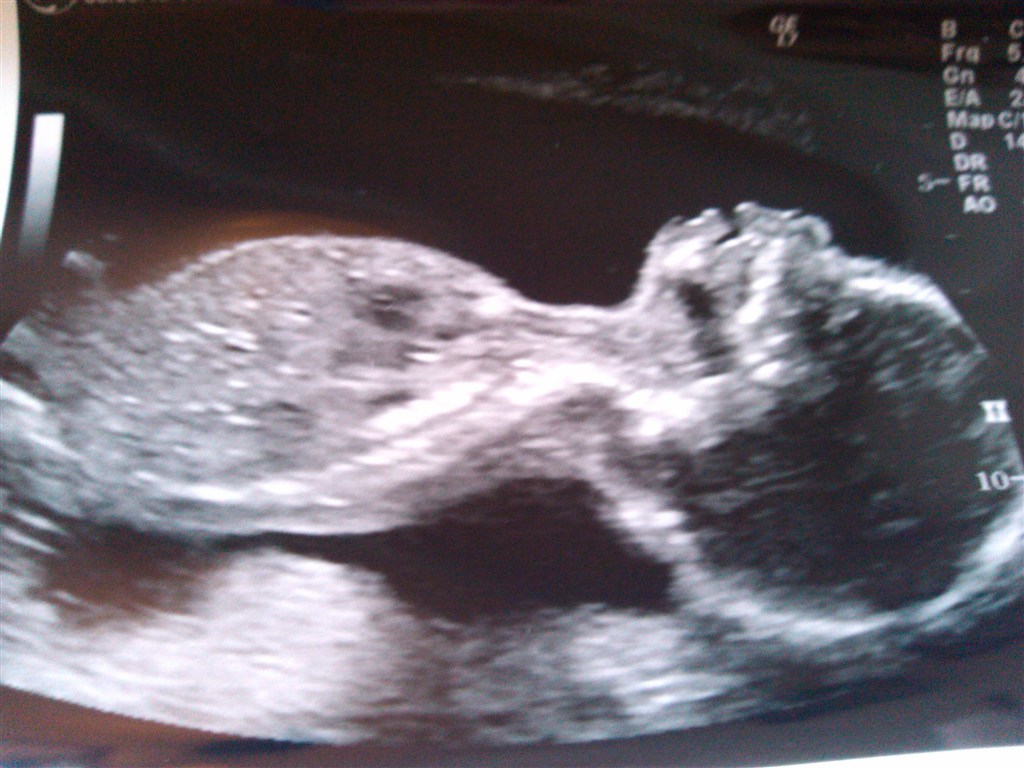

Jeg har også netop været til MD, vild fed oplevelse og fascinerende indblik man får i den lille babys verden!

Synes dog der fortsat er længe til december og overvejer en 3D scanning i efteråret, så vi kan få et gensyn med den lille prinsesse, inden hun kommer ud til os